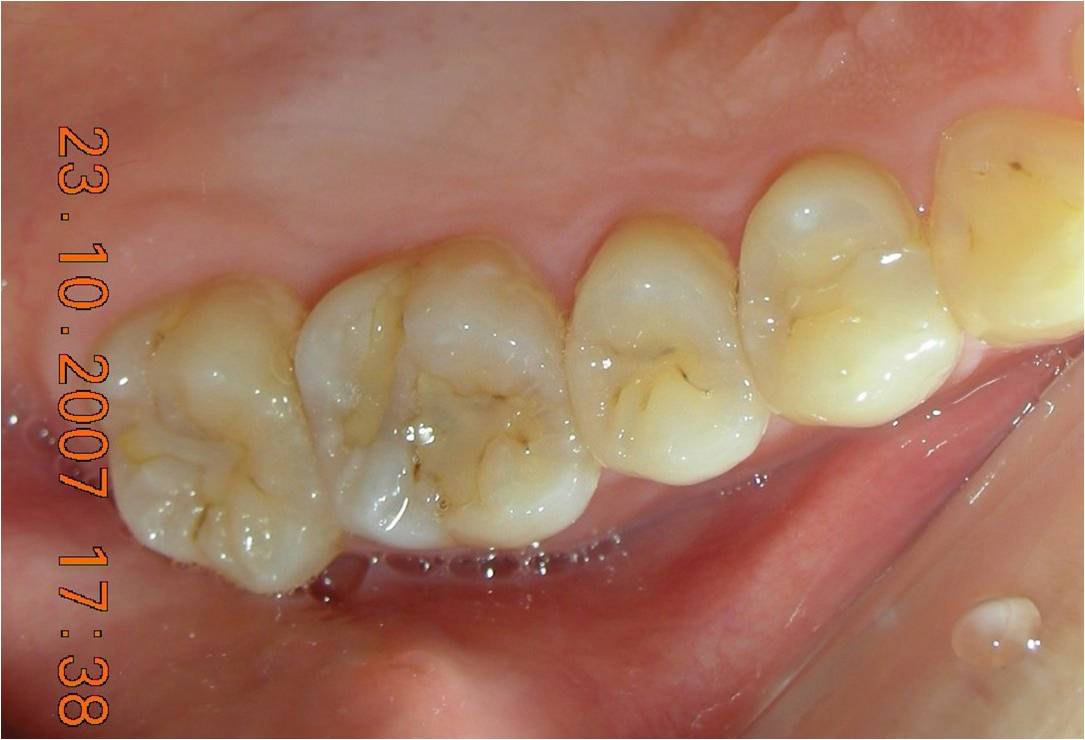

崁體窩洞製備